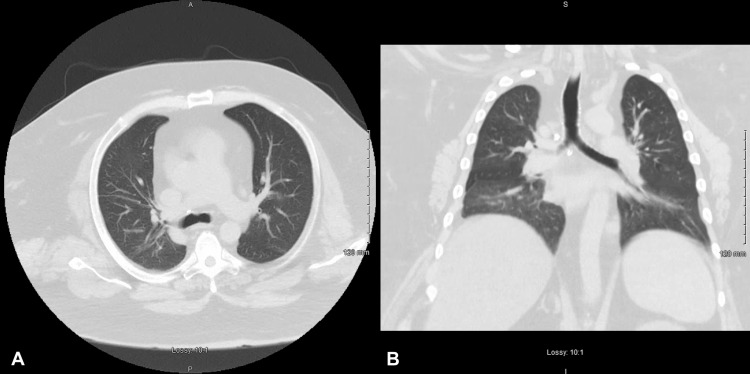

At one month follow-up in the pulmonary medicine clinic after hospital discharge, the patient reported that he had successfully quit smoking marijuana completely and denied any symptoms of shortness of breath. The patient had a repeat chest CT performed at this time, which demonstrated a complete resolution of the previous findings (Figure 2). Spirometry was also performed, which did not demonstrate evidence of obstructive lung disease. Since then, the patient has completely abstained from smoking marijuana and has not had recurrent bouts of pneumonitis. He is currently alive and well at the four-year follow-up mark. Repeat urinalyses have not demonstrated positivity for tetrahydrocannabinol.

In our patient’s case, we identified marijuana smoking as the etiology for his lung injury pattern based on a thorough diagnostic workup. Previous reports have described symptomatic marijuana-induced lung injury as a disease entity, satisfying criteria one and two. We ruled out autoimmune and infectious etiologies for the patient’s clinical manifestations through an extensive workup as detailed in the case presentation, satisfying criterion three. Additionally, since the patient’s symptoms resolved and never relapsed following discontinuation of marijuana smoking, criterion four is met. We are unable to satisfy criterion five, as it would have been unethical to administer a medication that has the potential to cause patient harm. One study by Yamauchi et al. examined the BAL cytology of patients with drug-induced pneumonitis. The study found that, in patients with DLI, the most common BAL finding was elevated lymphocyte cell fractions [ref. 9]. Consistent with this study, our patient’s BAL cytology also showed an elevated lymphocyte cell fraction, suggestive of DLI. Interestingly, the chest CT of our patient demonstrates diffuse bilateral patchy opacifications and similarities resembling what He et al. describe as a "tree-in-bloom" [ref. 5]. This "tree-in-bloom" appearance may be a radiologic pattern that some patients with marijuana-induced lung injury exhibit and warrants further study.

Marijuana, also commonly referred to as cannabis, is a commonly abused illicit substance that has gained worldwide popularity. Due to its common use, we believe marijuana-induced lung injury is a diagnosis that may increase in prevalence in the coming years. Its ability to produce a significant disease burden to patients requires further studies as it has only been previously reported in case studies. Consistent with other studies, we identified elevated lymphocyte cell fractions in our BAL and noted patchy opacifications with a "tree-in-bloom" pattern on chest CT. Clinicians should consider marijuana-induced lung injury in patients presenting with diffuse pulmonary opacifications after ruling out infectious and autoimmune etiologies. We aim to increase awareness of this pulmonary pathology by describing a unique patient case and sharing our radiologic, bronchoscopic, and laboratory findings.